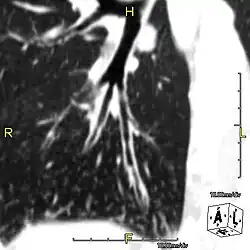

Oblique sagittal CT image showing lower lobe cylindrical bronchiectasis in the same patient

Around 80% of people with primary ciliary dyskinesia experience respiratory problems beginning within a day of birth. Many have a collapsed lobe of the lung and blood oxygen low enough to require treatment with supplemental oxygen.[1] Within the first few months of life, most develop a chronic mucus-producing cough and runny nose.[1] The main consequence of impaired ciliary function is reduced or absent mucus clearance from the lungs, and susceptibility to chronic recurrent respiratory infections, including sinusitis, bronchitis, pneumonia, and otitis media. Progressive damage to the respiratory system is common, including progressive bronchiectasis beginning in early childhood, and sinus disease (sometimes becoming severe in adults). However, diagnosis is often missed early in life despite the characteristic signs and symptoms.[2] In males, immotility of sperm can lead to infertility, although conception remains possible through the use of in vitro fertilization, there also are reported cases where sperm were able to move.[8] Trials have also shown that there is a marked reduction in fertility in females with Kartagener's syndrome due to dysfunction of the oviductal cilia.[9]